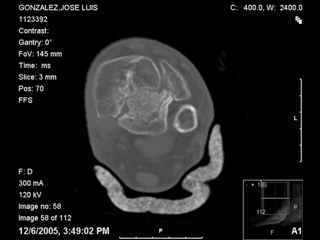

A 56 year old laborer fell off a wall approximately 5 months ago. He sustained an open pilon fracture. He was treated with debridement and external fixation. After he was treated for 4 months, the external fixator was removed.

I have attached his x-rays. I have also attached an WMV movie file of his axial CT (if you are unable to view this, I can post an MPEG file).